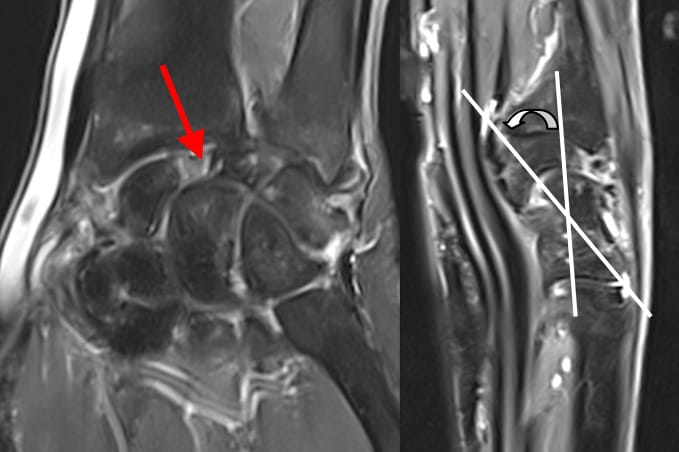

« SLAC wrist » (Scapho-Lunate Advanced Collapse)